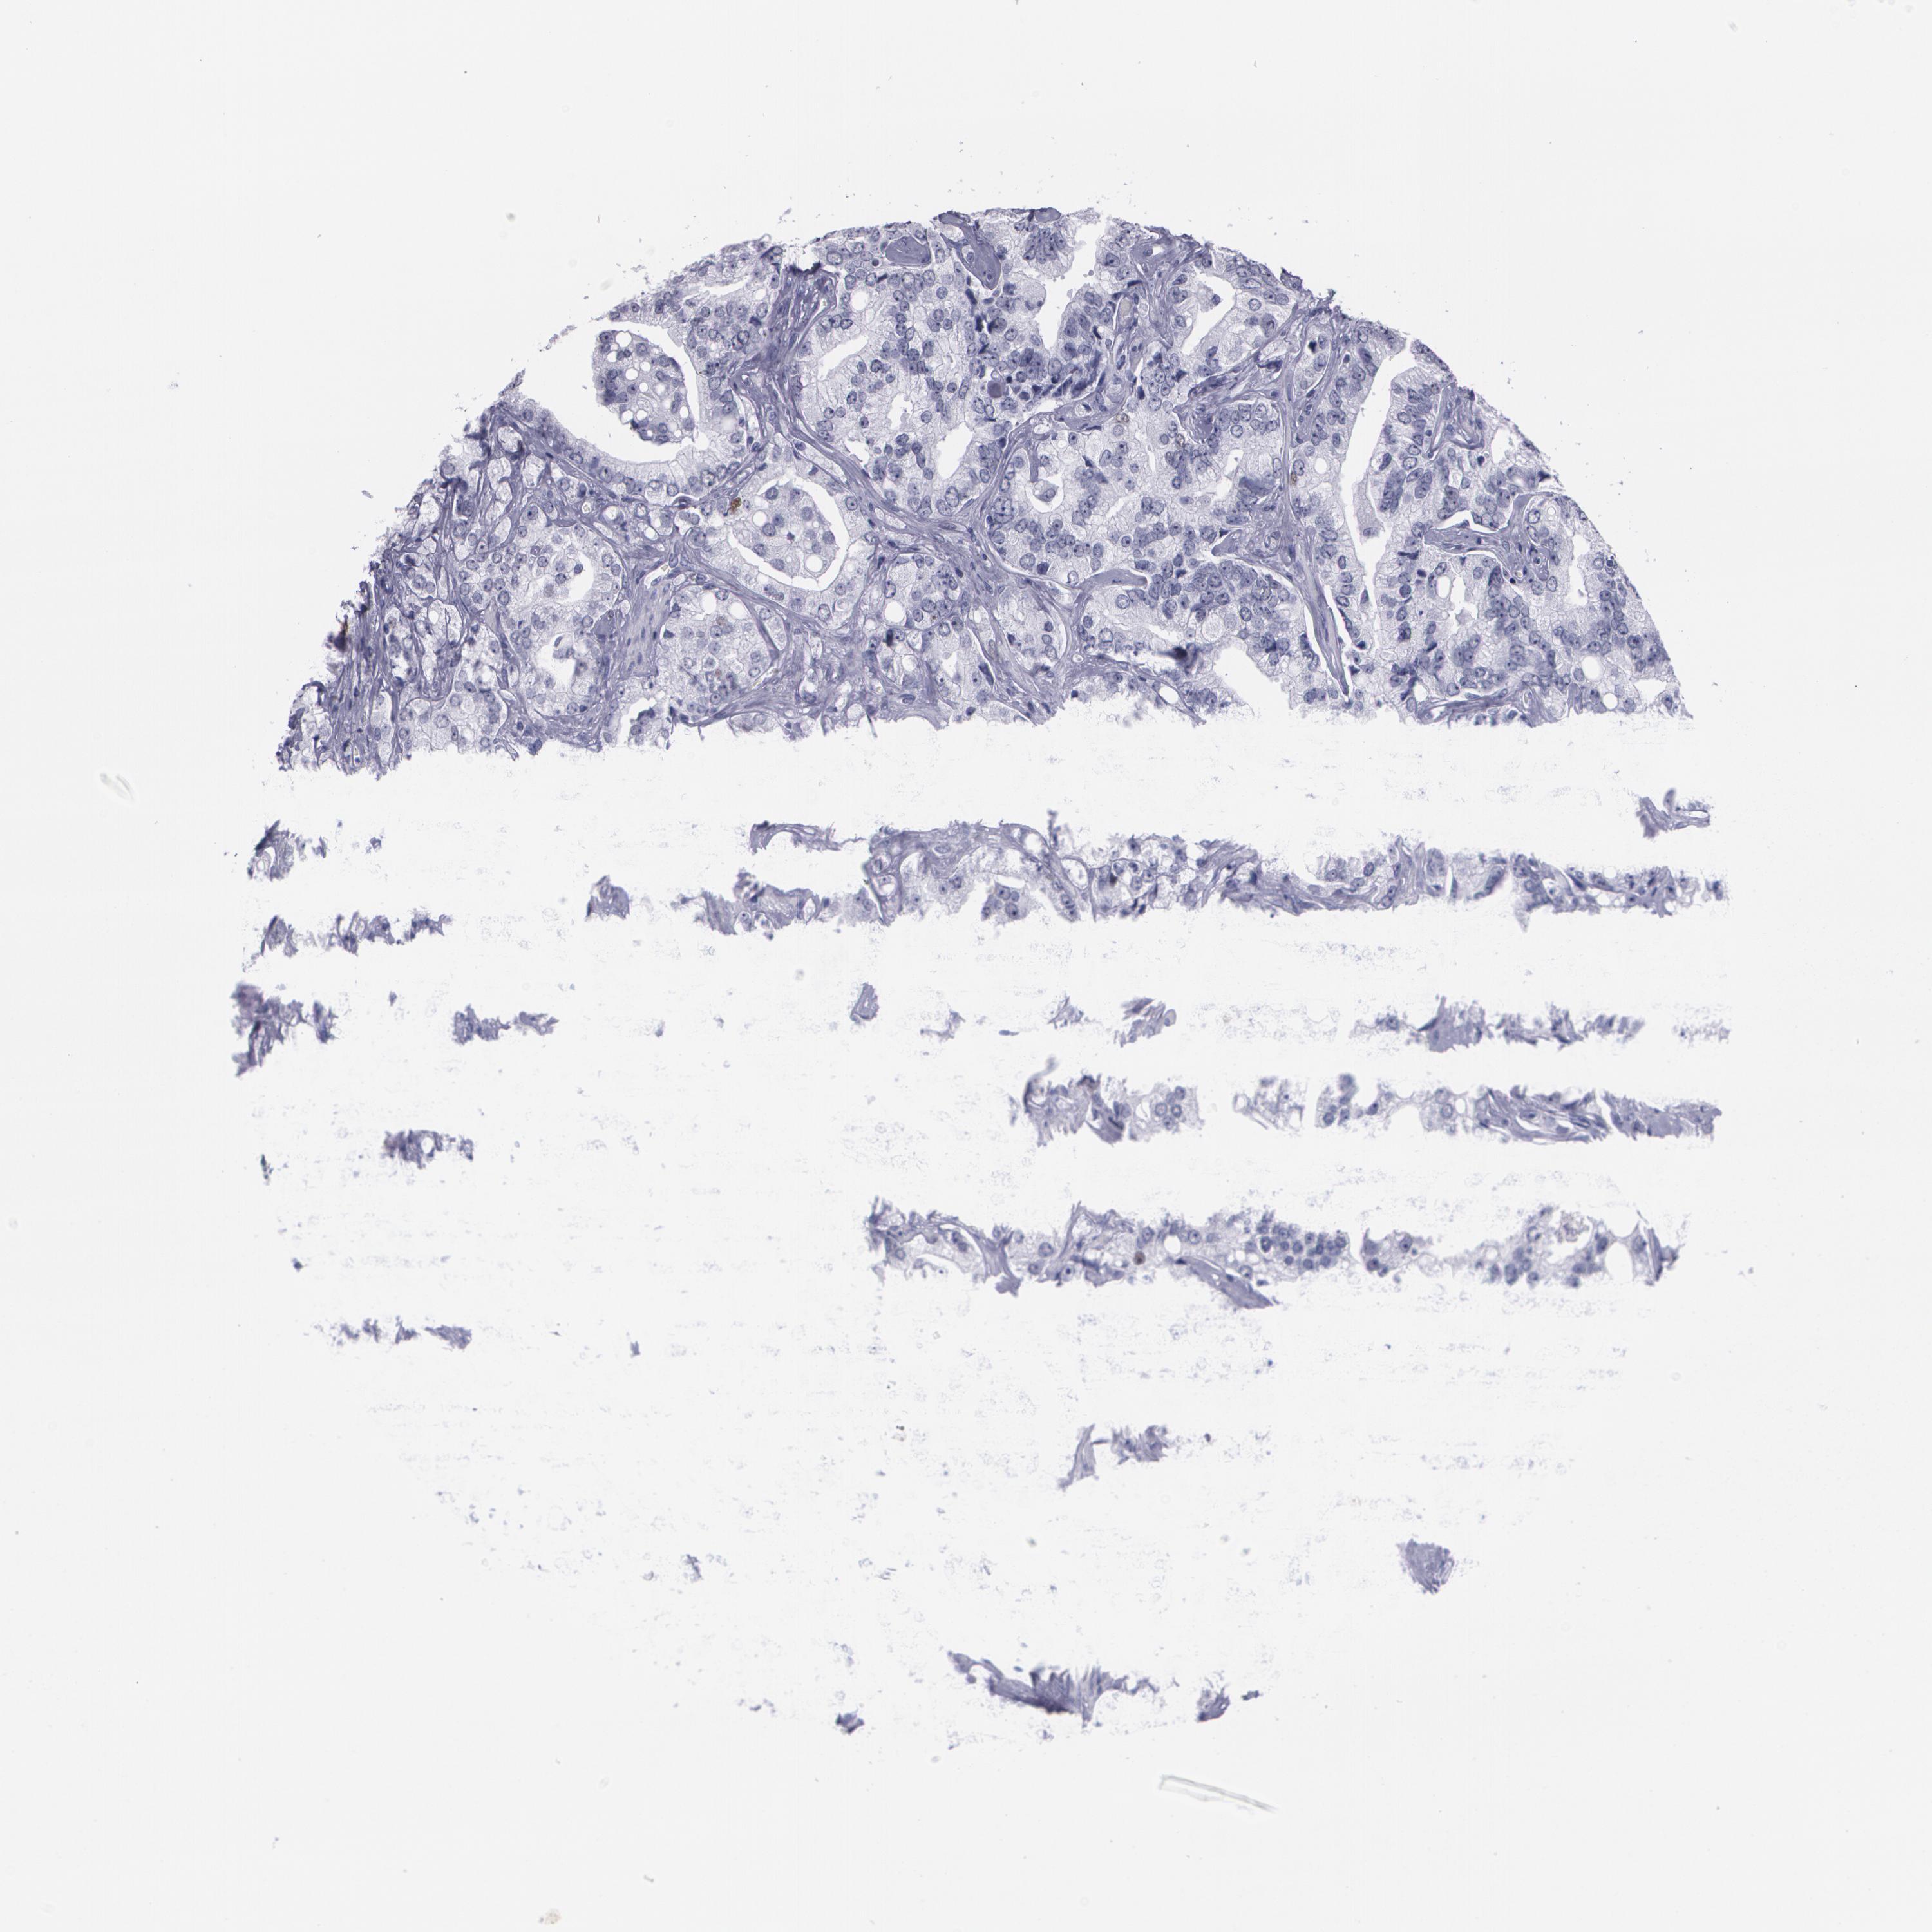

PROSTATE CANCER - Protein expressioni

A mouse-over function shows sample information and annotation data. Click on an image to view it in a full screen mode. Samples can be filtered based on level of antibody staining by selecting one or several of the following categories: high, medium, low and not detected. The assay and annotation is described here.

Note that samples used for immunohistochemistry by the Human Protein Atlas do not correspond to samples in the TCGA dataset.

Antibody stainingi

Antibody staining in the annotated cell types in the current human tissue is reported as not detected, low, medium, or high, based on conventional immunohistochemistry profiling in selected tissues. This score is based on the combination of the staining intensity and fraction of stained cells.

Each image is clickable and will lead to virtual microscopy that enables deeper exploration of all samples and also displays staining intensity scores, fraction scores and subcellular localization as well as patient and tissue information for each sample.

Antibody CAB002973

Antibody CAB039238

Antibody CAB039239

Antibody CAB072876

Staining

High

Medium

Low

Not detected

Intensity

Strong

Moderate

Weak

Negative

Quantity

>75%

75%-25%

<25%

None

Location

Nuclear

Cytoplasmic/membranous

Cytoplasmic/membranous,nuclear

Adenocarcinoma, Low grade

Adenocarcinoma, Medium grade

Adenocarcinoma, High grade

Adenocarcinoma, NOS